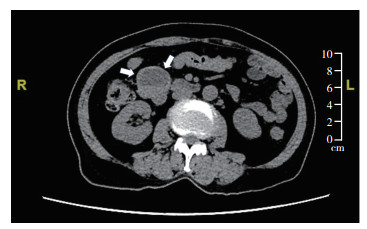

2 结果 2.1 临床特征15例BRAF突变型GIST患者中,男性8例,女性7例,男女比例1∶0.9,无明显性别差异。所有病例均发生于成年患者,发病年龄34~76岁,平均56岁,中位53岁(表 1)。临床上,大部分病例无明显临床症状,多为体检偶然发现(10例);少数表现为上腹部不适或疼痛(2例);另3例(20.0%)因胃癌根治术,被误以为肿大淋巴结而偶然发现。7例(46.7%)术前接受消化道内镜检查,内镜下绝大多数表现为隆起型肿块,黏膜表面常完整,少数伴有糜烂,无溃疡形成;而在超声内镜下表现为边界规则的实性肿块,内部回声欠均匀,彩色多普勒血流显像(color Doppler flow imaging, CDFI)可见血流信号较丰富,弹性成像质地较硬。8例(53.3%)术前接受腹盆部CT或MRI检查,多表现为消化道均质实性圆形或椭圆形肿块,少数伴有出血和囊性变(图 1)。15例均为原发肿瘤,肿瘤发生部位包括胃10例(66.7%)、十二指肠3例(20.0%)和空肠2例(13.3%)。发生于胃和小肠(包括十二指肠和空肠)的病例在性别、发病年龄和肿瘤最大径方面比较,差异均无统计学意义(均P > 0.05)。肿瘤以单发性为主(14/15,93.3%),仅1例(1/15,6.7%)为多发性,肿瘤数目为2个。肿瘤最大径0.5~25 cm,平均3.7 cm,中位1.5 cm,6例为肿瘤最大径≤1 cm的微小GIST。多发性肿瘤仅计入体积最大者。

| 注 腹部CT扫描示十二指肠降段囊实性结节状肿块(箭头示) 图 1 BRAF突变型胃肠间质瘤的影像学表现 Fig.1 Imaging manifestations of BRAF-mutated gastrointestinal stromal tumors |